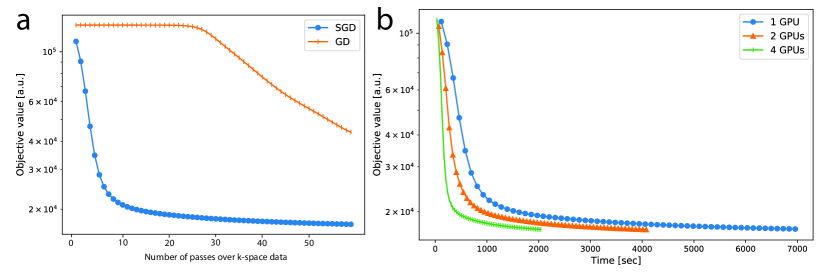

4.1.2 Second DCE dataset

Convergence plots for the second DCE dataset reconstructed with 20 frames are shown in Figure 5a and b. Each marker indicates a pass through the entire k-space dataset. Figure 5a compares SGD with one GPU to GD. After 60 passes of k-space data, SGD is mostly converged, whereas GD only attains the objective value of about the fourth pass for SGD. Figure 5b compares the convergence of SGD with multiple GPUs. The convergence rates are similar in terms of number of passes. As for overall computation time, there is a small overhead going from one GPU to two GPUs, resulting in a 1.7x speedup instead of the ideal 2x speedup. We conjecture that this is due to data transferring between GPUs. From two to four GPUs, there is not much additional overhead, resulting in a speedup of almost 2x. The overall speedup from one to four GPUs is about 3.4.

The benefit of using SGD compared to conventional iterative algorithms can be seen in Figure 5. For GD, each pass of the k-space data only computes one iteration, whereas for SGD, each pass computes many iterations. Even though each SGD iteration makes fewer progress than GD, SGD reaches an approximate minimum faster by performing many more iterations. In our experiment with 20 frames, we observe that GD is approximately 15x slower, and expect this difference to be even greater with 500 frames. However, the current SGD reconstruction time is still long, ranging from 6 hours to 42 hours, depending on the number of coils and the reconstruction matrix size. We remain hopeful that with additional computing devices, either with large number of GPUs or cloud computing, reconstruction time can be brought to a reasonable range. This is partly supported by Figure 5b, which shows that the speedup of using multiple GPUs is almost linear from one to four GPUs.